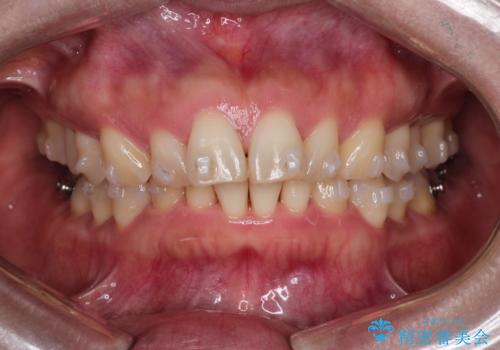

【インビザライン】出っ歯を治したい

- 前歯が出ていることを主訴に来院されました。

インビザラインにて臼歯部の遠心移動及びIPRを行なっています。

叢生量が多いケースでしたが、綺麗な歯並びとなり患者様にも満足していただきました。